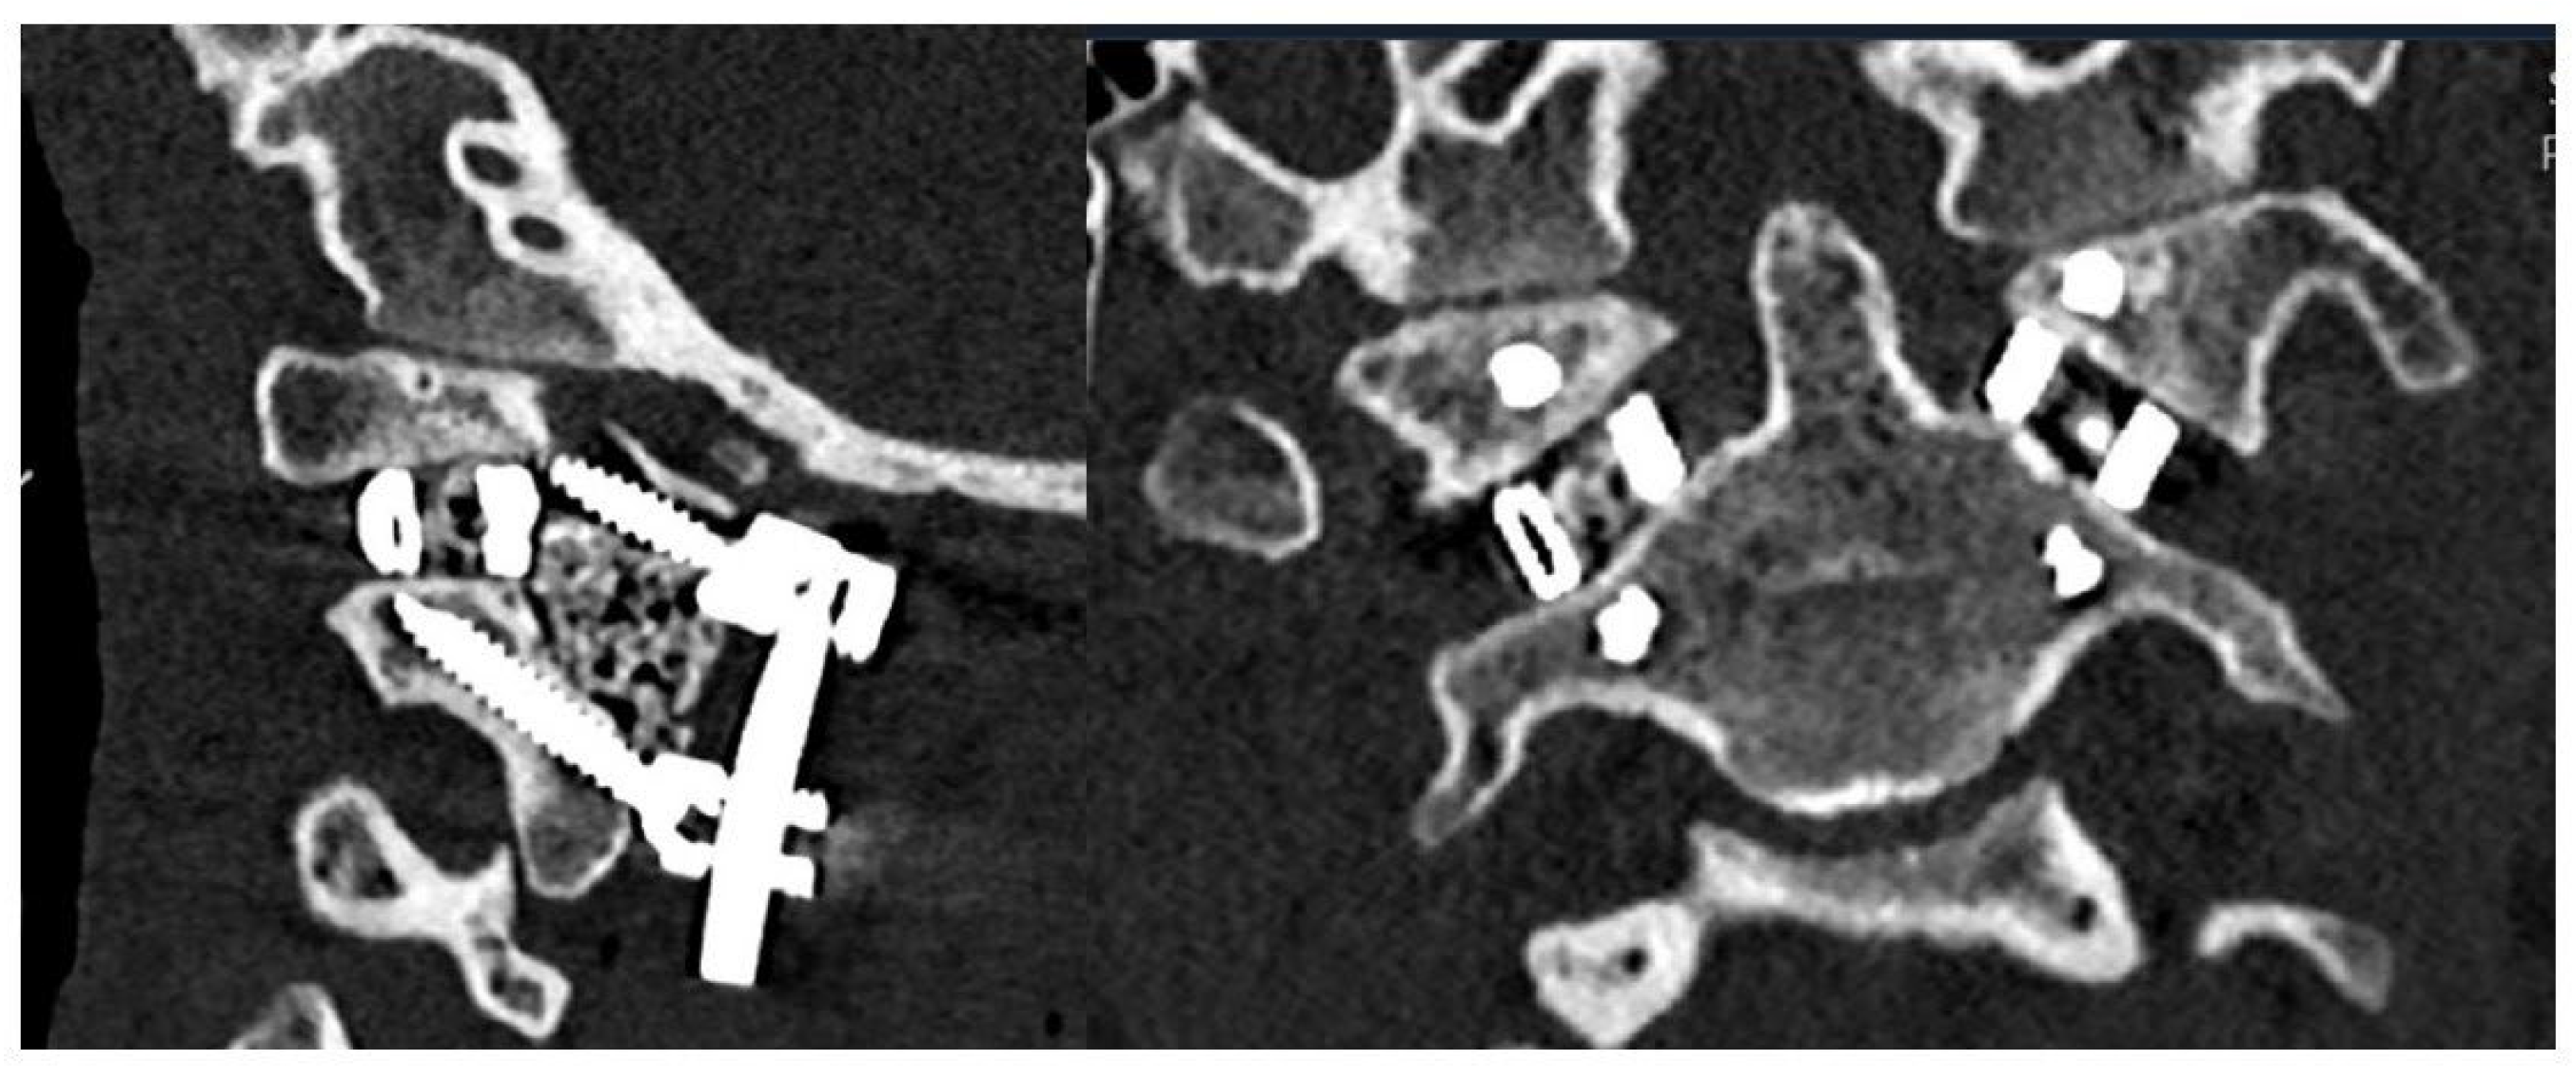

3.2. Surgical Approach